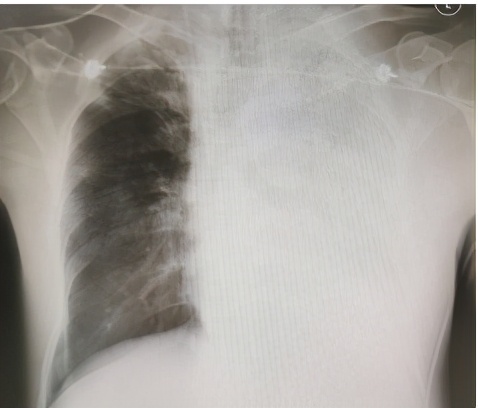

半月前,李大伯因为发热1天到浙江省立同德医院就诊,当时主要表现为发热,轻微气急,做了肺部CT,提示左肺有大片的炎症。但初始的治疗似乎并没有有效阻止病情的进展,李大伯高热不退,气更急了,自己觉得透不过气来,24小时不到再次复查胸片,结果让人大吃一惊,左边肺部基本全白。因此,李大伯被紧急收治到ICU。

图为李大伯的胸片